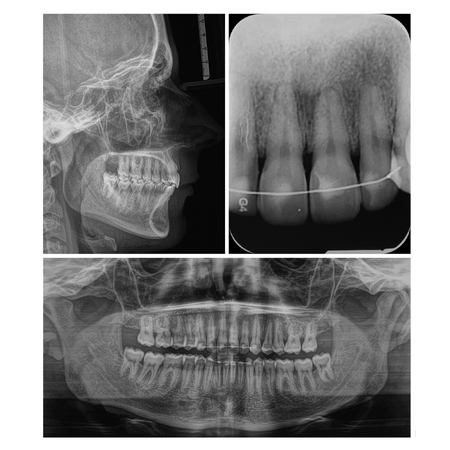

INTRODUÇÃO: O gerenciamento dos espaços das agenesias dentárias é frequentemente relatado como um desafio adicional para o tratamento ortodôntico e, quando associado à má oclusão esquelética, torna o tratamento mais complexo. OBJETIVO: Neste relato de caso, objetivou-se apresentar um tratamento ortopédico seguido de tratamento ortodôntico compensatório de um paciente Classe III esquelética severa com agenesia dentária múltipla. RELATO DE CASO: Paciente do sexo masculino, com 14 anos de idade, teve um plano de tratamento atípico, inicialmente tratado com máscara facial...

INTRODUÇÃO: O gerenciamento dos espaços das agenesias dentárias é frequentemente relatado como um desafio adicional para o tratamento ortodôntico e, quando associado à má oclusão esquelética, torna o tratamento mais complexo. OBJETIVO: Neste relato de caso, objetivou-se apresentar um tratamento ortopédico seguido de tratamento ortodôntico compensatório de um paciente Classe III esquelética severa com agenesia dentária múltipla. RELATO DE CASO: Paciente do sexo masculino, com...

INTRODUCTION: Space management of tooth agenesis is often reported as an additional challenge for orthodontic treatment and, when associated with skeletal malocclusion, makes the treatment more complex. OBJECTIVE: The objective of this case report was to present an orthopedic treatment followed by comprehensive orthodontic treatment of a severe skeletal Class III patient with multiple tooth agenesis. CASE REPORT: A 14-year-old male had an atypical treatment plan, starting with facemask...